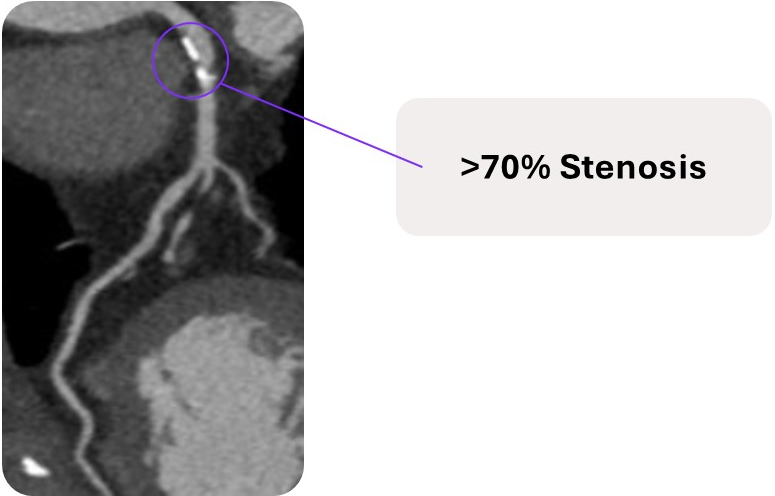

Traditional NITs vs. Heartflow | |||

Stress Echocardiogram | SPECT and PET | CCTA | Heartflow FFRCT Analysis |